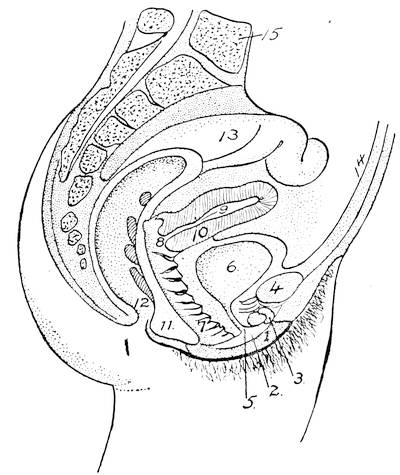

Mons of Venus, labia majora, minora, vestibule, bulbs, clitoris, Bartholinian glands, hymen, vagina, uterus, broad and round ligaments, viiitubes, ovaries, Graafian follicle, ovum.

Function of ovaries, ovum, Graafian follicle, tubes, menstruation, function of uterus, female ejaculation, function of vagina, Bartholinian glands, of clitoris, course of the sexual act.

At the time when the urethra, the sexual ducts and the intestine still open into the sac-like tube, the so-called cloaca, there is distinguishable on the exterior surface of the body, corresponding to the position of the cloaca, a certain depression called the cloacal depression. When the intestine is separated from the cloaca by the septum, the later perineum, the exterior cloacal depression is cut into two, the anal and the urogenital depressions. Between the urogenital depression, later called the genital groove, exteriorly and the urogenital sinus interiorly, there is only a dividing membrane, the urogenital membrane which later on breaks through and transforms the entire sinus into a shallow depression, termed the vestibule.

In the female the vestibule, or the shallow depression which was formed through the breaking through of the urogenital membrane, remains open throughout life, and is termed the vestibule of the vulva. From the sides of the lower part of the sinus a pair of evaginations are formed and give rise to the Bartholinian glands. The vestibule being in fact the open sinus urogenitalis, the urethra and the vagina naturally have their orifices in the same.

The genital tubercle ceases to grow in the female and becomes the clitoris. The genital folds or the lips of the vestibule become prolonged and form the labia minora or the nymphae. The genital swelling increases in size through adipose and fibrous tissue. The part situated on the ventral side of the clitoris becomes the mons veneris, while the lateral parts are converted into the labia majora of the vulva.